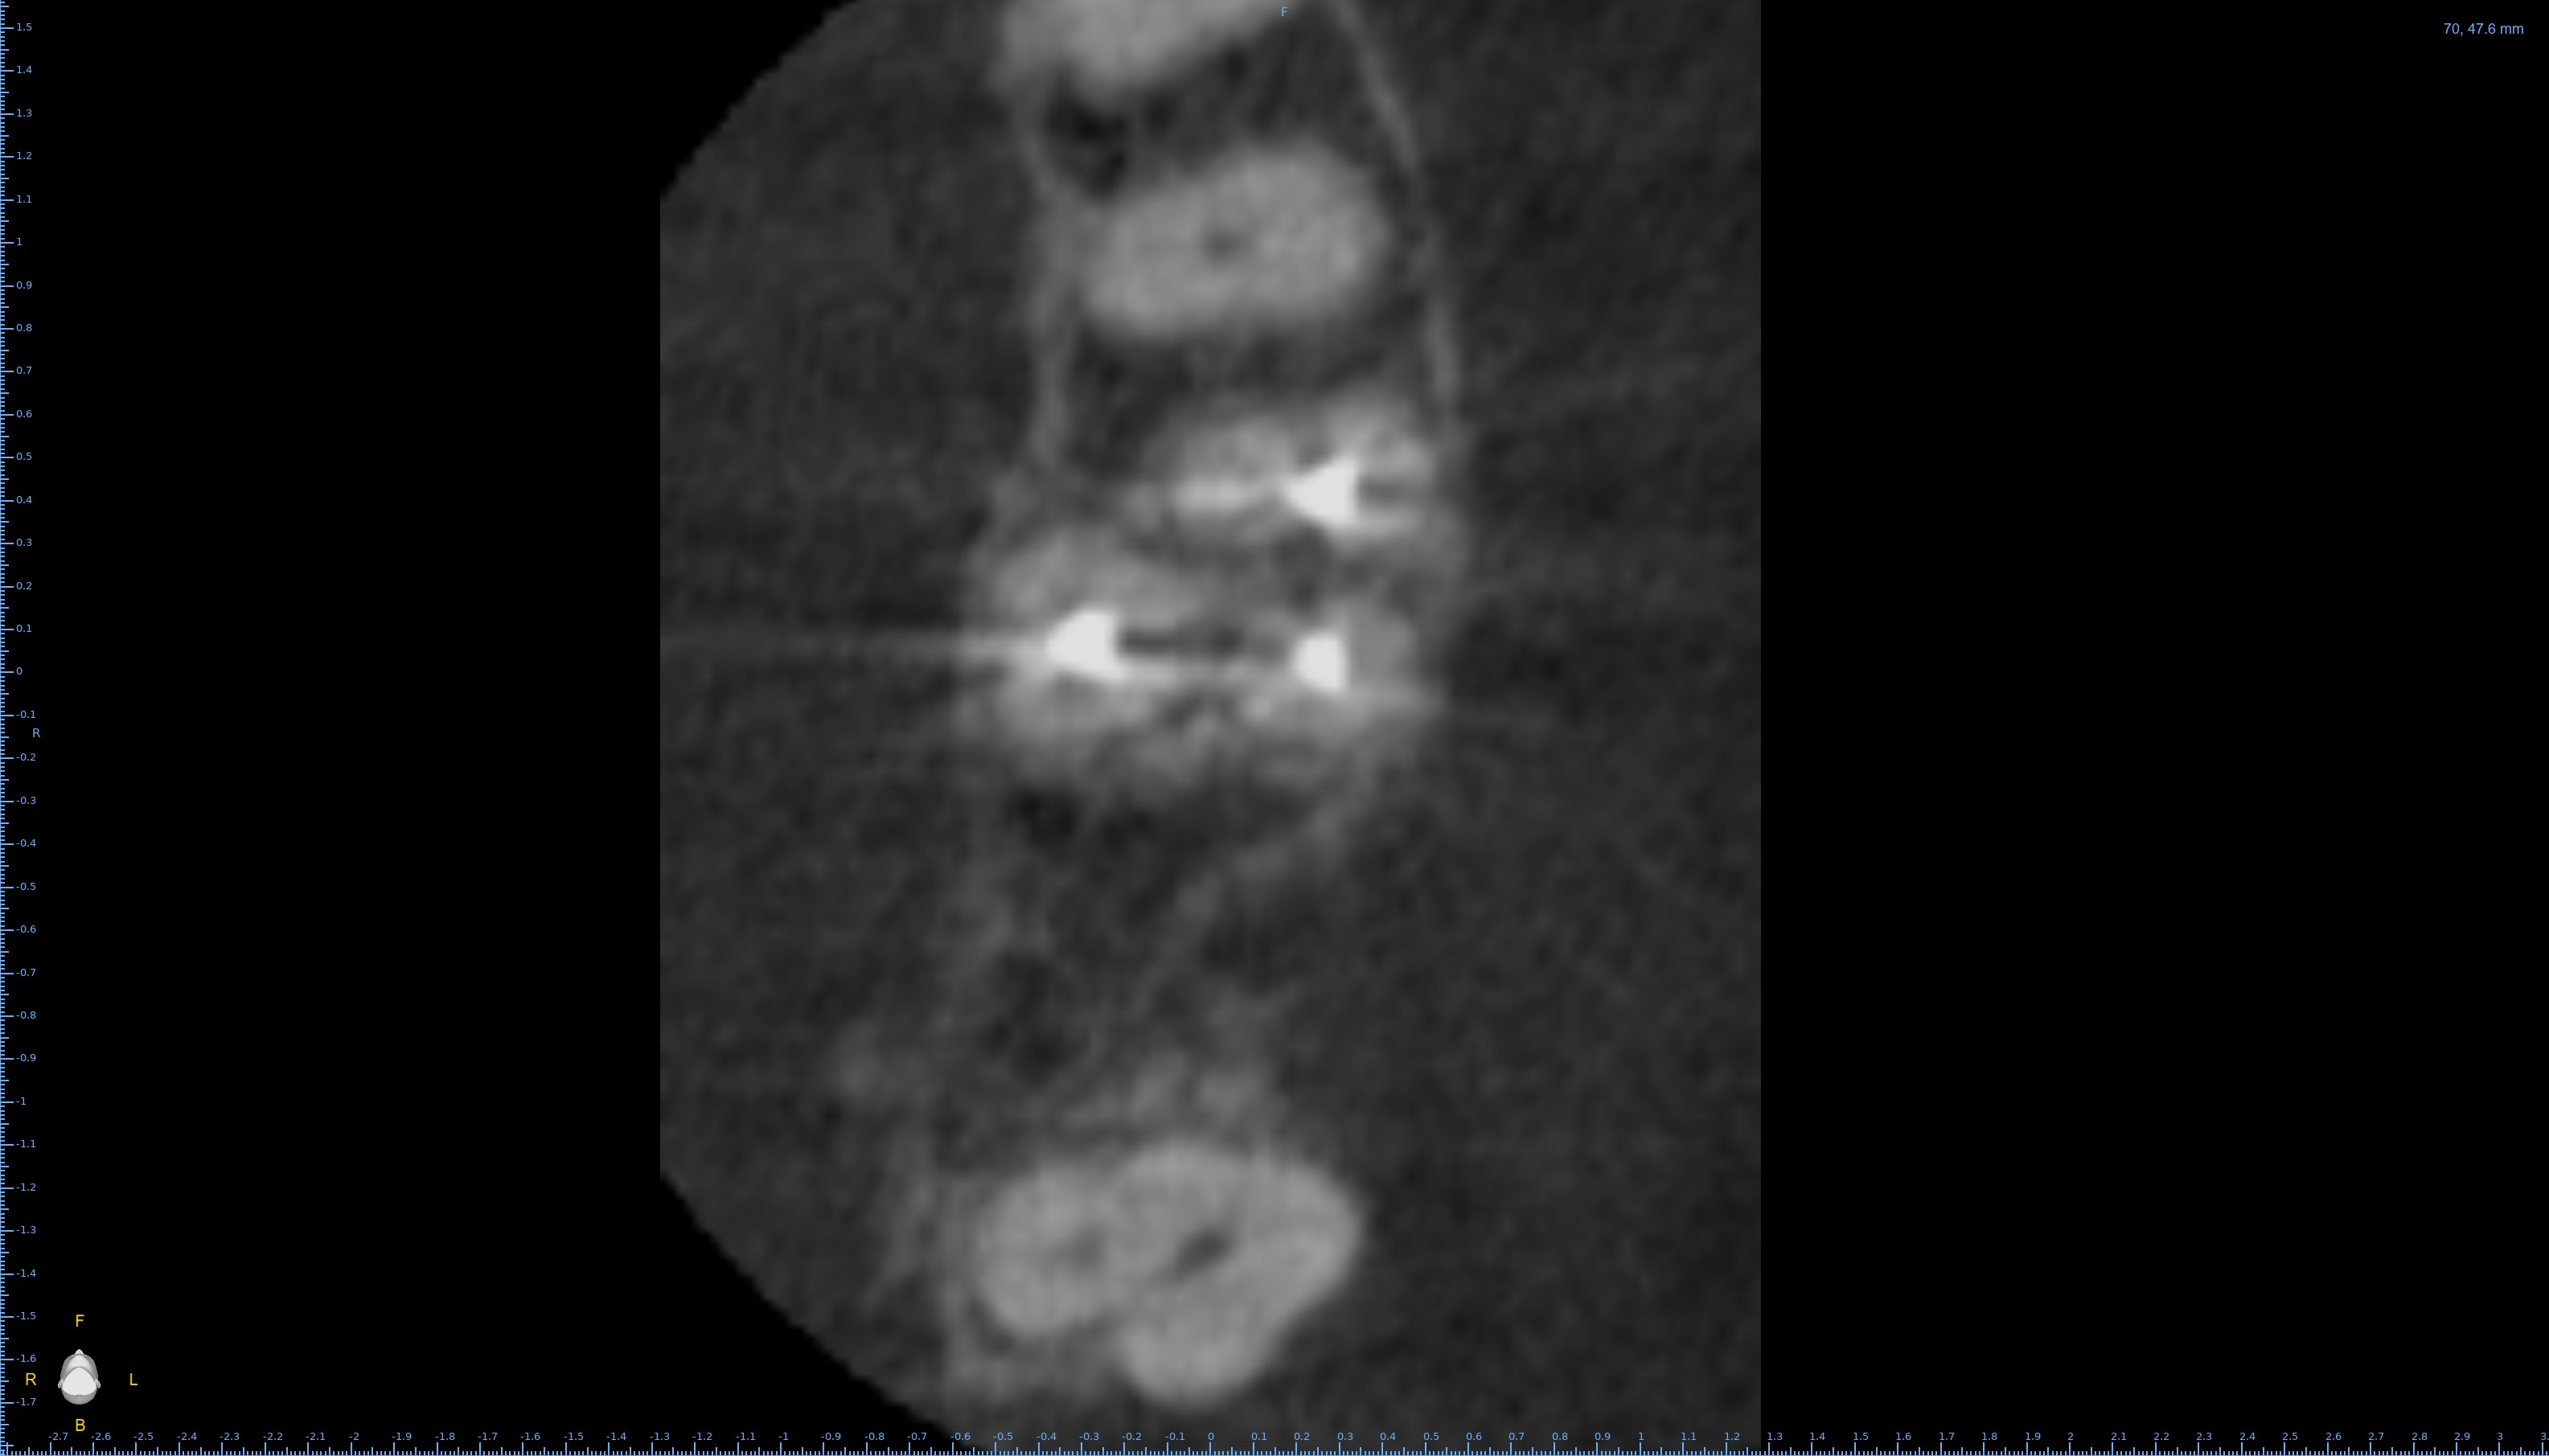

Pour répondre à Dentarue: je viens de faire des coupes horizontale et centrées sur la racine vestibulaire en tournant autour d'un potentiel MV2. La gutta et le ciment font un joli artefact radio donc ce n'est pas concluant.

On le voit très bien sur ta 3d.

Aucune gloire, on ne voit que ça.

Chercher une deuxième entrée en vestibulaire quand on voit sur cette coupe et sur la coupe horizontale que c’est le palatin qui n’est pas obturé, … les mots me manquent.

Il cherche en vestibulaire de MV mais c’est en palatin de MV qu’il fallait chercher, cela me semblait aller sans dire ☝️

Tout est sur la 3d.

Le MV2 n’est pas très proche de la furcation mais plutôt plus mésial que le MV1. Il est très visible à la radio et ne doit pas être bien compliqué à traiter, mais pour ça il faut s’en donner les moyens et ça commence par la digue.

Tu nous dis qu’il n’y a pas de MV2 et tu nous montres des coupes où il saute aux yeux puis tu vois la patiente entre deux pour désobturer MV1 sans digue… et laisser MV2 non traité…

Il est plus mésial.

Si ce qu’on voit est le MV1 désobturé, le MV2 est à peu de chose près là où est ta flèche verte. Son entrée est souvent plus apicale. Le trouver est une chose, le négocier une autre, souvent bien chronophage.